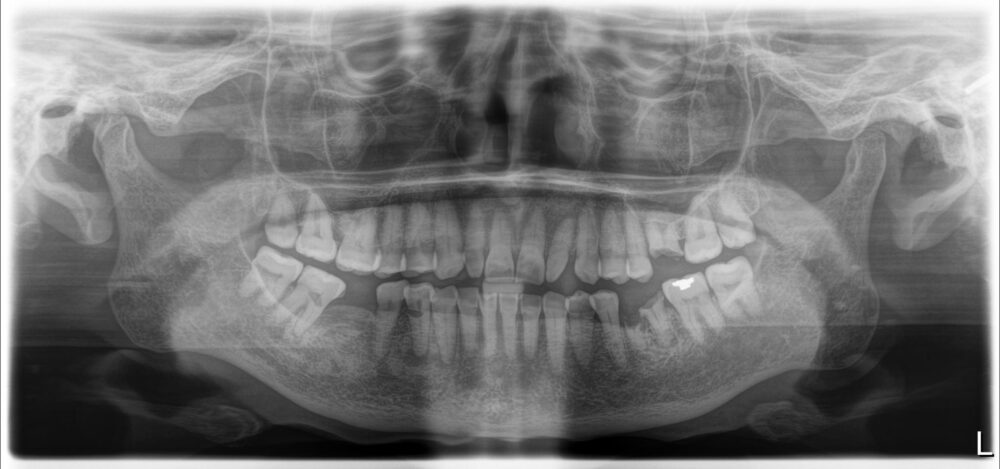

症例1

治療前

| 主訴 | 歯を入れたい |

| 診断 |

左下6残根 |

| 治療内容 | 左下6抜歯、インプラント補綴 |

| 年齢・性別 |

78歳、女性 |

| 治療期間 |

6ヶ月 |

| 治療費用 | 診査診断¥22000+インプラント一次オペ(京セラ)¥275000+GBR¥110000+上部構造(ジルコニア)¥143000 総額¥550000 |

| リスク・副作用 | インプラント周囲炎、インプラント上部構造の緩み |